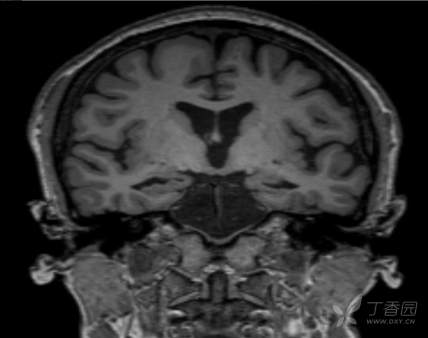

颈部、脑部动脉均未见明显异常,MRI+MRA+T2Flair+SWI+冠状位: 双侧额顶叶皮层下散在小缺血灶;双 侧海马萎缩2级,小脑蚓部、右侧额 叶微出血灶,如下图所示: